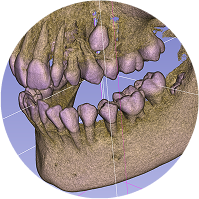

Tecnología avanzada

Ofrezco tratamientos de vanguardia que aseguran comodidad y eficacia para todos mis pacientes.